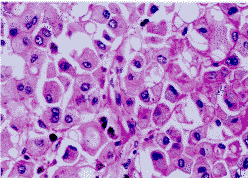

2.1 巨检及镜检 梭形肿块大小9 cm×7 cm×5 cm,表面粗糙,无包膜,附有部分肋骨。切面略呈结节状,境界清,如鱼肉状,黄白相间,部分区域灰红色有散在出血灶。光镜下见瘤细胞呈卵圆或多边形,胞浆丰富嗜酸性,有的瘤细胞胞浆空泡内可见圆形淡红均质或透明的包涵体(图1),未见横纹。核偏位呈泡状,核膜厚,部分核仁明显,核分裂象易见。偶见少数畸形巨核或多核瘤巨细胞。瘤细胞排列多样,大多呈巢团状浸润(图2),有的围绕血管呈放射状排列,有的呈腺泡状,有的血窦丰富呈副节瘤样结构,也有弥漫成片如淋巴瘤样。

图1 肿瘤细胞呈卵圆或多边形,泡状核,胞浆丰富嗜酸性,并见胞浆空泡及包涵体.HE×400